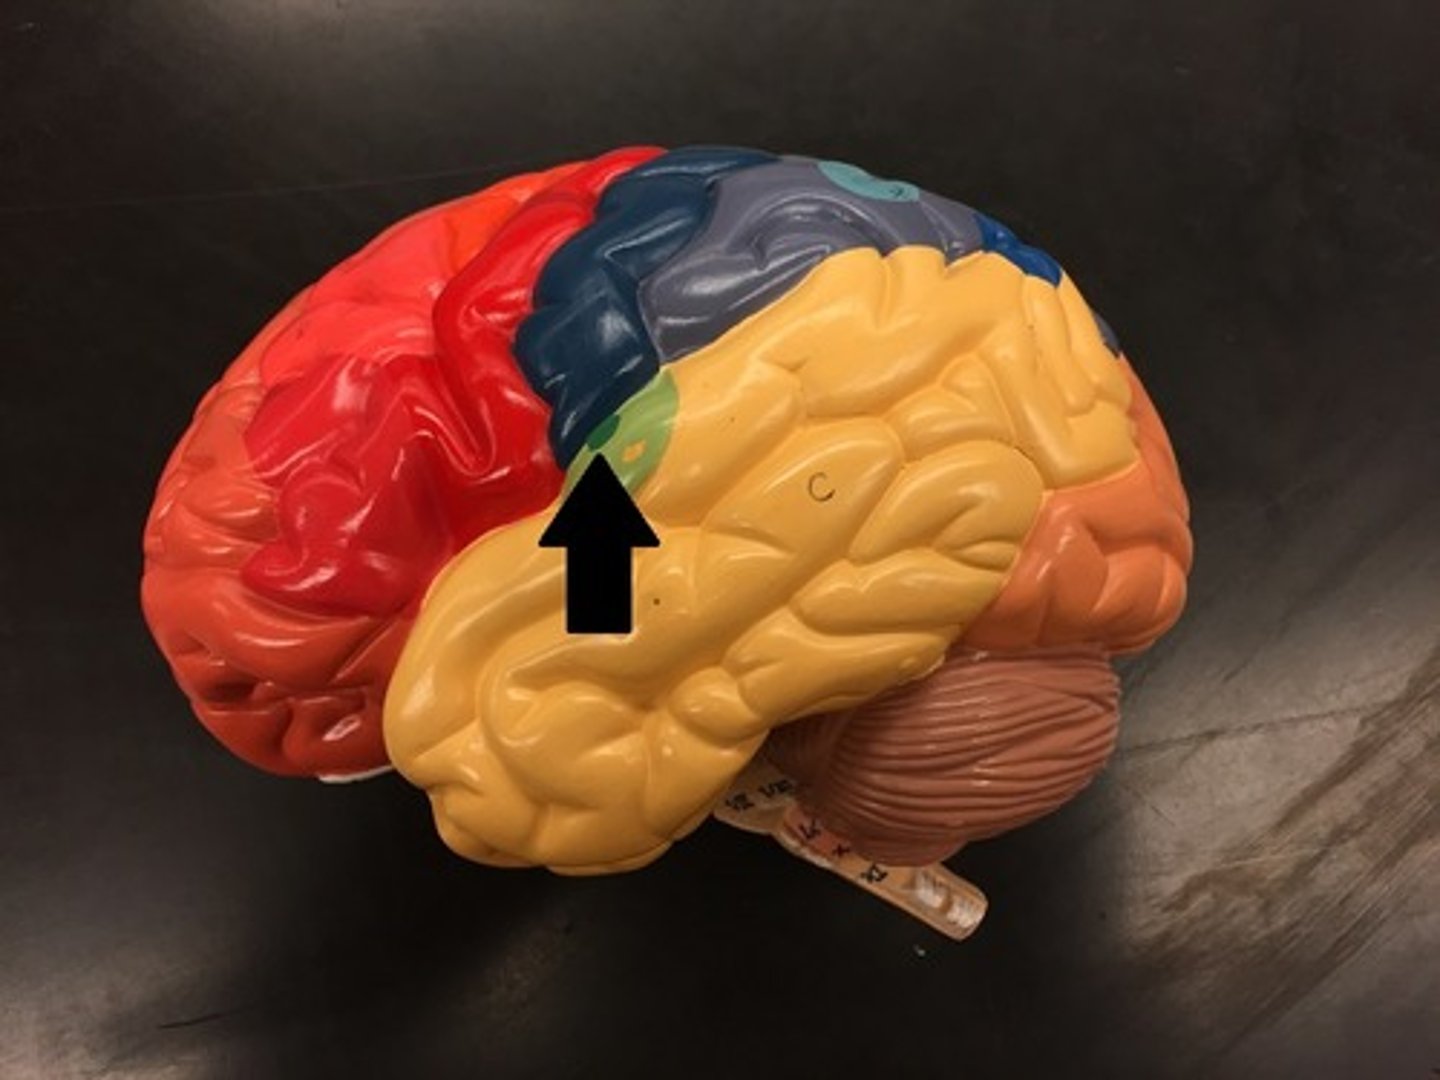

frontal lobe

temporal lobe

parietal lobe

occipital lobe

Broca's area

Prefrontal cortex

Premotor cortex

Wernicke's area